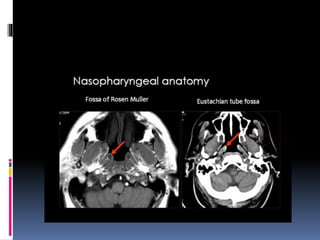

 Coronal sections of the nasopharynx show the-

eustachian tube opening, torus tubaris. Fossa of

rosenmuller and the adenoids, if present.

 Asymmetry of the Fossa of rosenmuller should

be looked for.